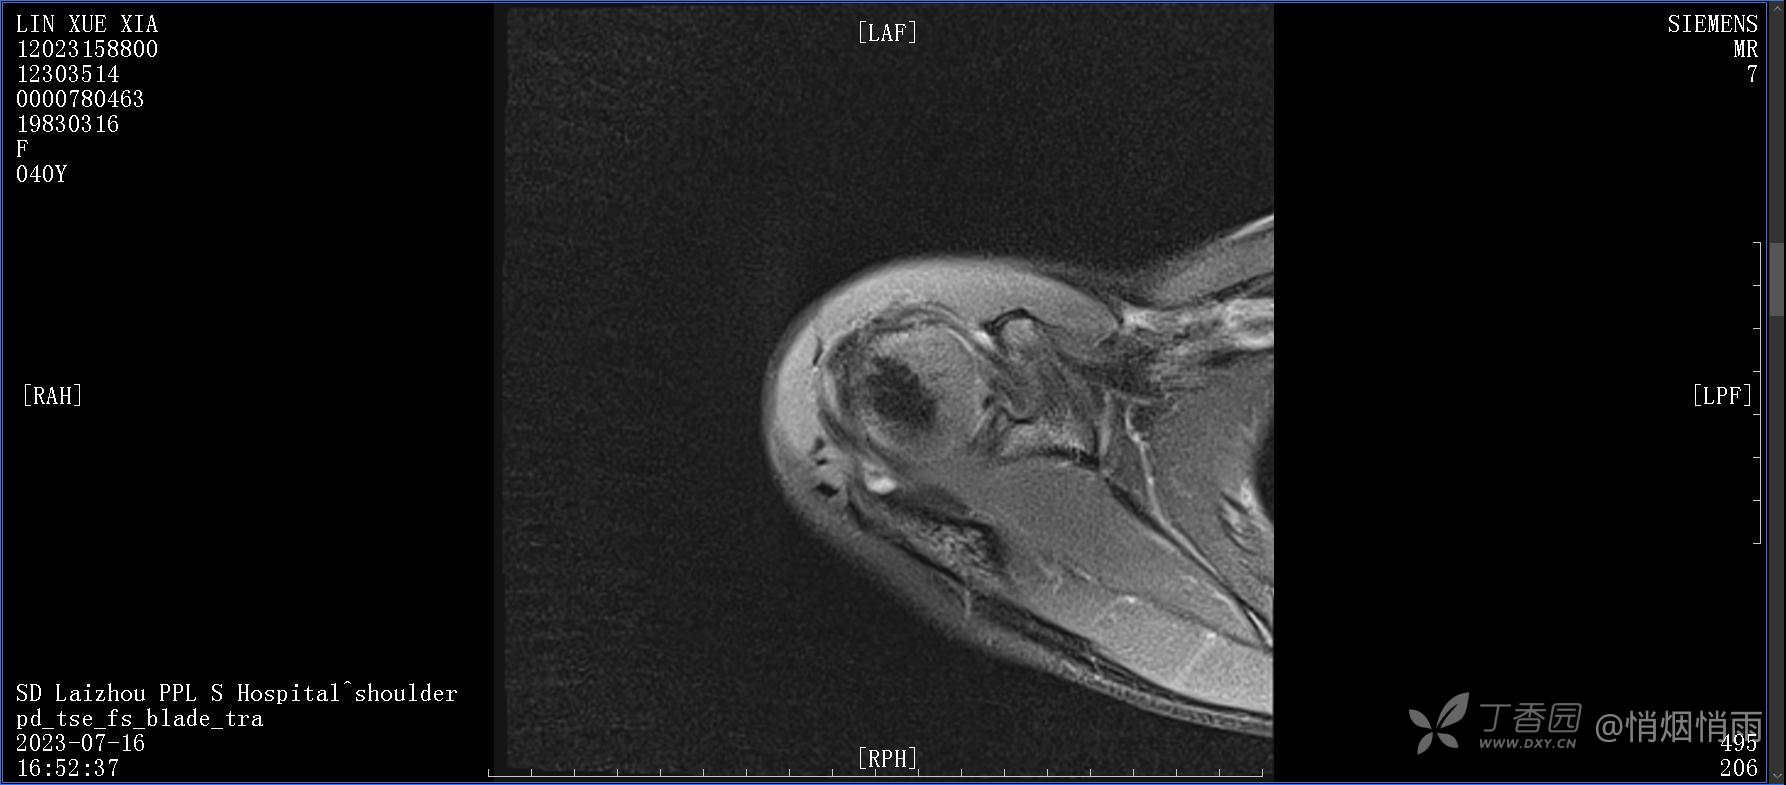

查体:右肩关节局部轻度肿胀,肩胛区压痛明显,痛处不固定,肩关节痛性活动受限,jobe test(+),lift -off test(+),中指、环指感觉较余指减退,余肢端感觉及血运情况可。

目前的诊断,暂时依据辅助检查诊为肩袖损伤,但是患者疼痛的性质和特点,却不是单纯的肩袖损伤所致。考虑过胸廓出口综合征,但是该疾病会出现肩胛区的疼痛吗?(由于考虑到费用的问题,没再进行下一步的检查)带状疱疹会有如此的症状吗?